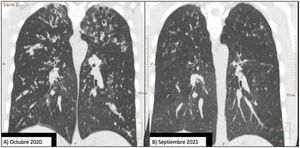

Comparison of 2 coronal chest CT reconstructions. Image (A) shows extensive bilateral bronchiectasis, with significant thickening of the bronchial walls, mucus plugging, and a tree-in-bud pattern. After 1 year of treatment with elaxacaftor/tezacaftor/ivacaftor, image (B), bronchiectasis is significantly reduced and practically resolved.

Given the patient's clinical situation, he was enrolled in an early access program for treatment with CFTR modulators, a compassionate use program known as MyMAPs. In October 2020, treatment began with elexacaftor/tezacaftor/ivacaftor (ETI) 75/50/100mg, 2 tablets at breakfast and 1 tablet of ivacaftor 150mg at dinner. After 1 year of follow-up, the patient had improved significantly. Lung function had increased by 25% (FEV1: 2450ml, 55.8%), respiratory exacerbations had dramatically reduced – no events since the start of treatment – cough and bronchorrhea had resolved, and exercise tolerance had improved. Follow-up chest CT showed a significant improvement in mucus plugging, a significant reduction in the size and number of bronchiectasis, some of which had disappeared (Fig. 1B), and a reduction in the size of the bulla in the right upper apex (Fig. 2B). The Bhalla score increased from 6 to 17 points in September 2021. The patient was therefore taken off the lung transplantation waiting list.